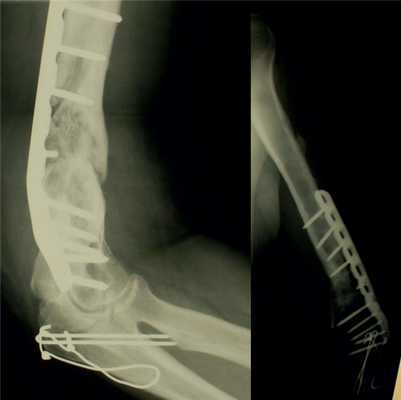

Консолидация перелома при кровоснабжаемой костной пластике была достигнута в 36 (88%) случаях в течение 4-6 мес (рис. 2): Рис. 2. Результаты оперативного лечения с использованием кровоснабжаемой костной пластикой. в группе применения малоберцового трансплантата консолидация была достигнута в 33 случаях, в группе трансплантата из мыщелка бедренной кости — в 3 случаях.

Рис. 11. Пациентка Н. Оперативное лечение: резекция зоны ложного сустава левой плечевой кости, остеосинтез пластиной и винтами. Пластика свободным кровоснабжаемым трансплантатом из внутреннего мыщелка бедренной кости.

Рис. 12. Рентгенограммы пациентки Н. после операции.

Рис. 13. Рентгенограммы пациентки Н. через 8 мес после операции.